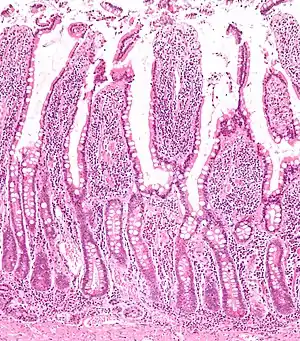

Micrograph of the small intestine mucosa showing the intestinal glands - bottom 1/3 of image. H&E stain. | |